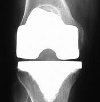

Ревизия коленного сустава. Операция по замене ранее созданного искусственного сустава. Возможна также полная переустановка систем и частичная замена изношенных компонентов. Ревизионный эндопротез выполняется при ограничении движений сустава, износа, повреждения или смещения частей искусственного сустава, развитии инфекции в протезном суставе, переломах большеберцовой кости или бедренная кость около протеза, нестабильность надколенника. Пациент может быть направлен на операцию по эндопротезу травматологом, хирургом-ортопедом или ревматологом.